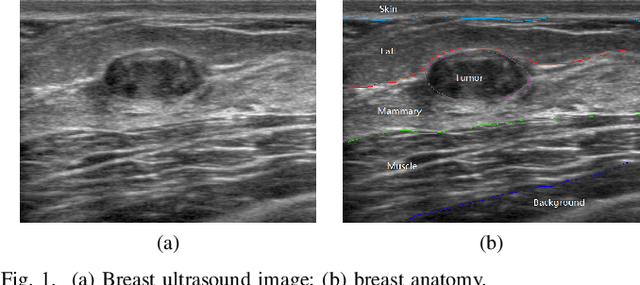

Abstract:Breast cancer is one of the most serious disease affecting women's health. Due to low cost, portable, no radiation, and high efficiency, breast ultrasound (BUS) imaging is the most popular approach for diagnosing early breast cancer. However, ultrasound images are low resolution and poor quality. Thus, developing accurate detection system is a challenging task. In this paper, we propose a fully automatic segmentation algorithm consisting of two parts: fuzzy fully convolutional network and accurately fine-tuning post-processing based on breast anatomy constraints. In the first part, the image is preprocessed by contrast enhancement, and wavelet features are employed for image augmentation. A fuzzy membership function transforms the augmented BUS images into fuzzy domain. The features from convolutional layers are processed using fuzzy logic as well. The conditional random fields (CRFs) post-process the segmentation result. The location relation among the breast anatomy layers is utilized to improve the performance. The proposed method is applied to the dataset with 325 BUS images, and achieves state-of-art performance compared with that of existing methods with true positive rate 90.33%, false positive rate 9.00%, and intersection over union (IoU) 81.29% on tumor category, and overall intersection over union (mIoU) 80.47% over five categories: fat layer, mammary layer, muscle layer, background, and tumor.